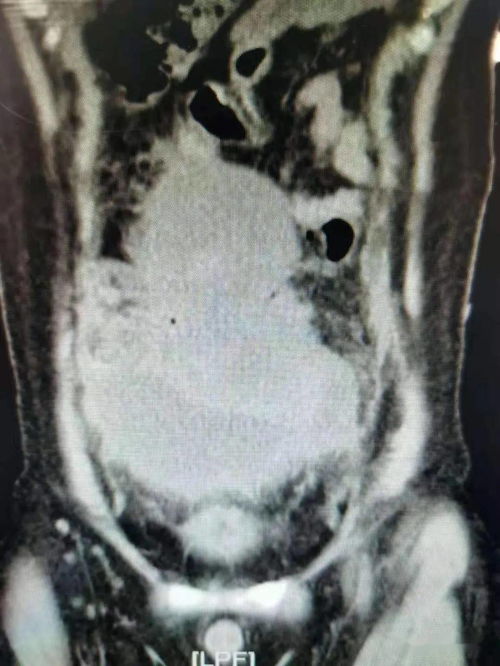

伤害感受性疼痛:当肿瘤直接侵犯皮肤、肌肉、骨骼或内脏时,你会感受到钝痛或锐痛。例如,骨转移导致的局部骨质疼痛,如椎体转移可能引发颈背部剧痛。

混合性疼痛:结合上述两种特征,多数晚期癌痛属于此类。例如,肿瘤原发灶与转移灶共同作用,导致持续加重的疼痛。

肿瘤直接引起的疼痛:如肺癌胸膜侵犯导致的胸痛。